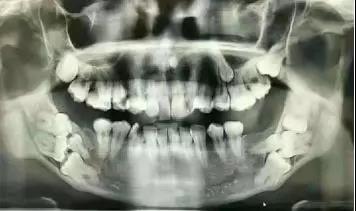

近中阻生智齿,也就是图中1、2两颗横着向牙列方向长的智齿,非常容易将邻近的牙“顶坏”,所以不得不将这两颗牙拔掉。像智齿这样的下颌槽牙的牙根离面部神经非常近,一不小心就可能伤到神经,导致面部没有知觉。而牙片可以清晰地看到牙根与神经的距离,确定拔牙是不是有风险,这也是为什么拔牙都要拍牙片的原因。这口牙只能用“出车祸”来形容了。本以为下颌大牙先天性缺失,不曾想是牙胚的生长方向错了,大牙长不出来。

②曲面断层或者CBCT:曲面断层多用于检查口腔整体状况,例如种植手术前查看牙槽骨骨量、下颌神经位置以及确定种植方案。